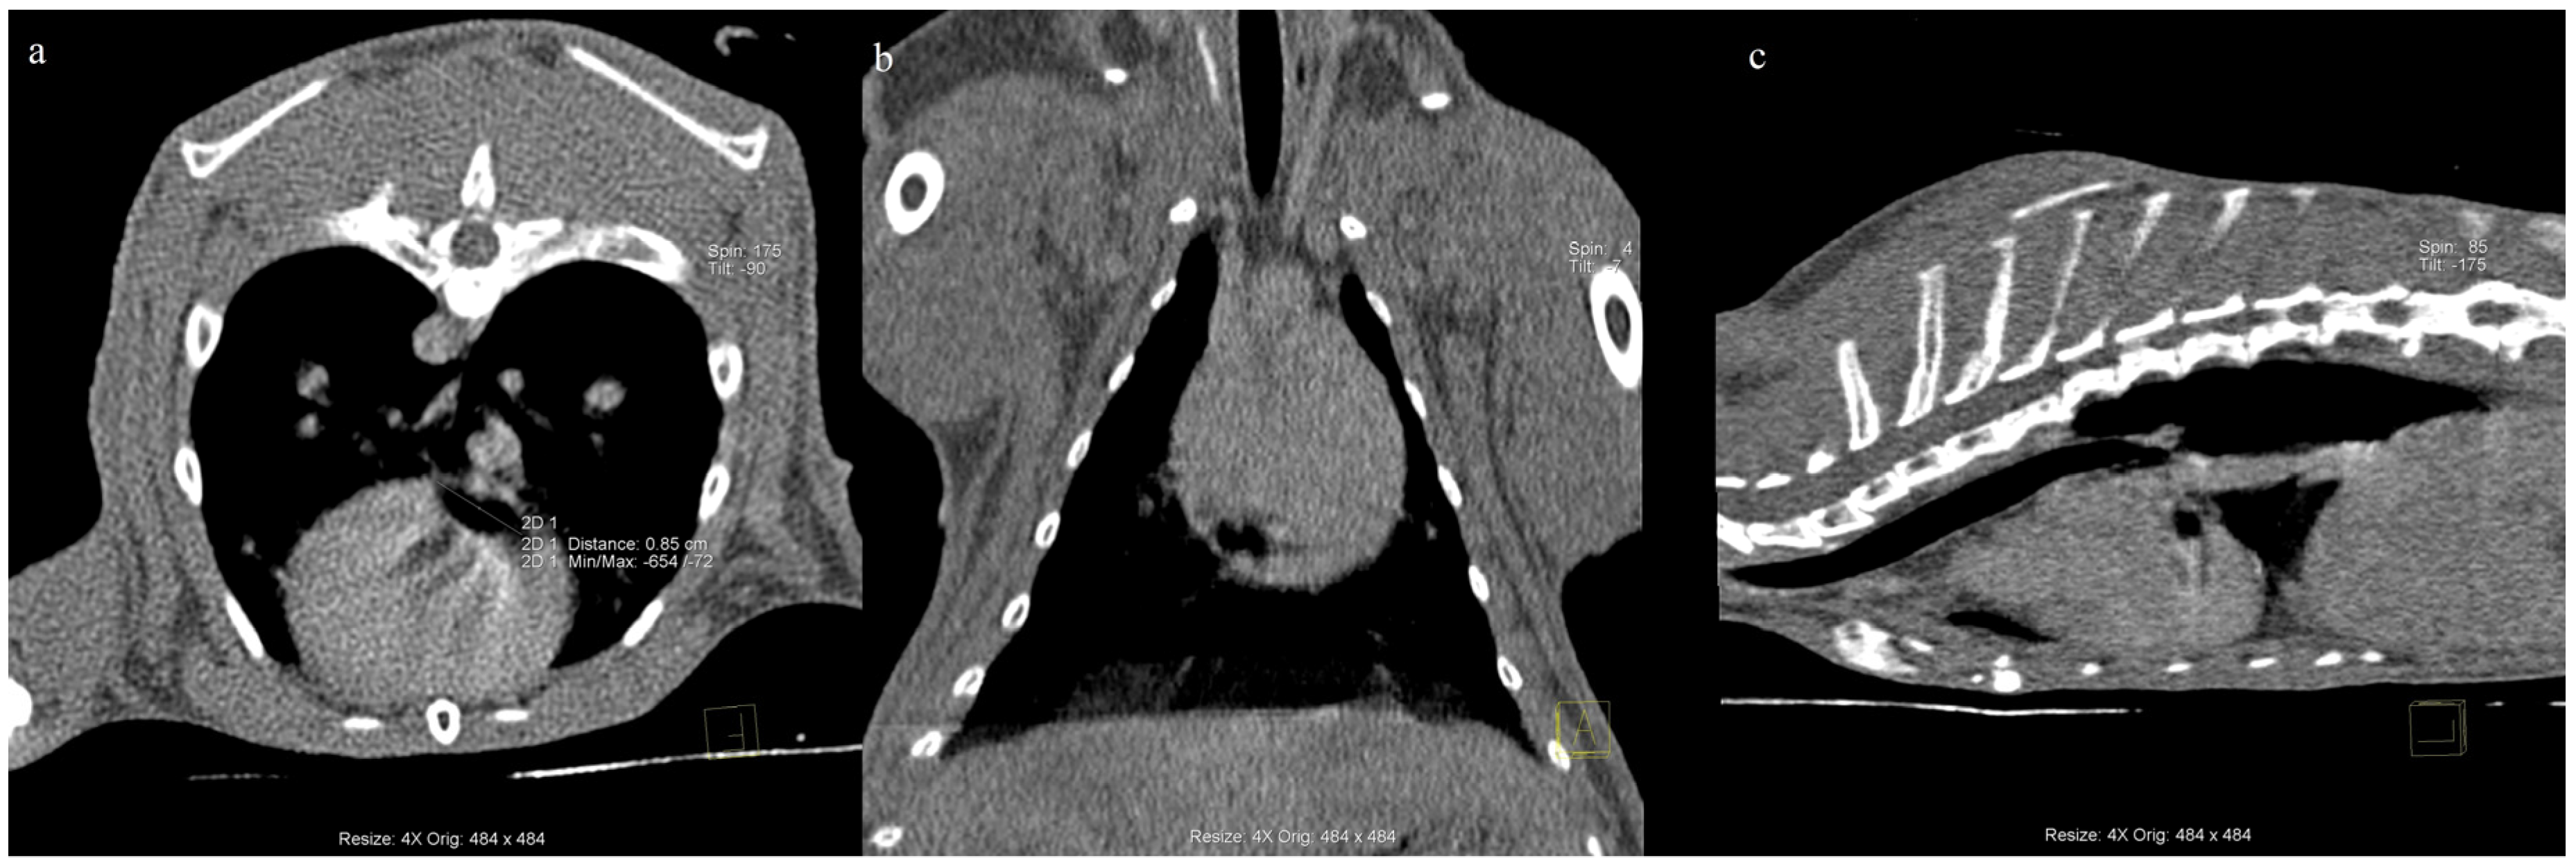

Tracheal Hemangioma Causing Lung Emphysema and Pneumopericardium in a Rabbit—A Case Report

2. History and Case Presentation